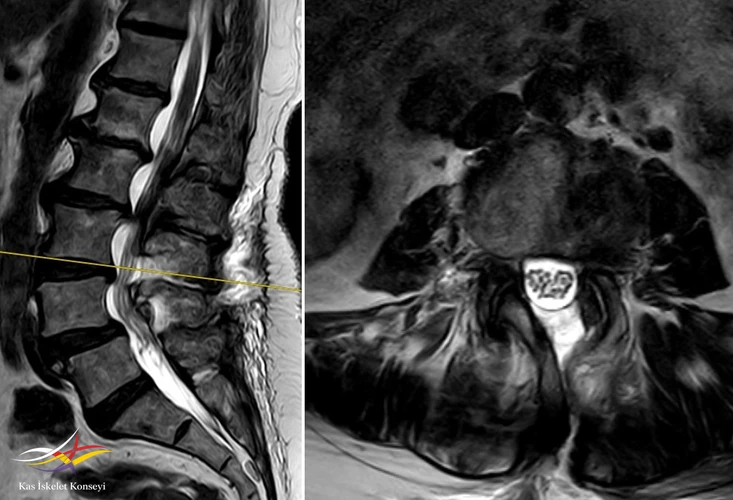

Resim 7. Ameliyat sonrası MRG: L3-4 seviyesindeki dekompresyon görülmekte.